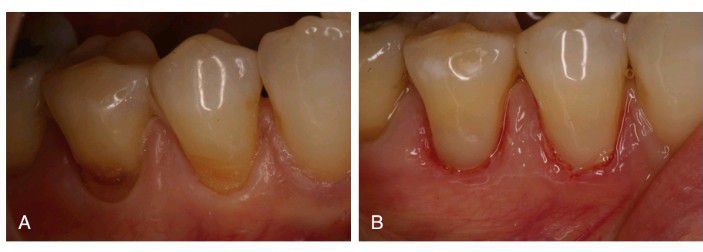

Restoration of root surface lesions

surface lesions. A, Abrasion/erosion lesions on the facial surface of mandibular premolars. B, Restorations with resin-modified glass ionomer cement and composite.